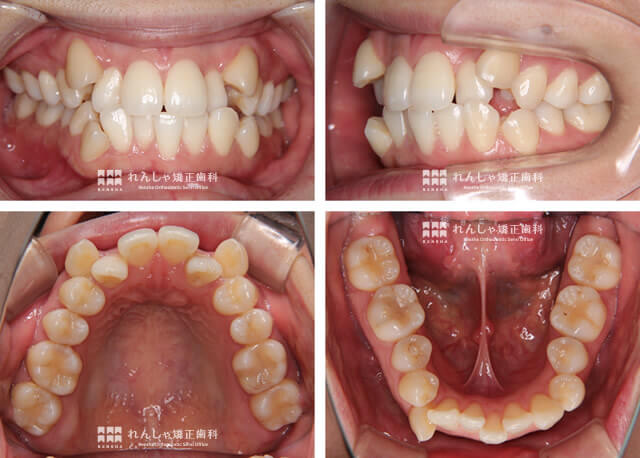

大人の矯正症例 E.Kさん治療記録

今回ご紹介するのは、明るくほがらかな笑顔のE.Kさんの症例。治療前の歯並びは、かなりガタガタ(叢生)で、八重歯が目立つ状態でした。矯正治療するきっかけは、ご結婚を間近に控えられていたこと、それに歯科衛生士であるご友人に勧められたからなのだとか。

治療に際しては、上下左右の永久歯を4本抜歯し、がたつきの改善を行いました。

悪い歯並びの代表とされるのが八重歯

永久前歯4本と6番目(6歳臼歯)は小学校低学年で萌えますが、前歯と臼歯の間の永久歯3本は小学校高学年頃に生え変わりが完了します。

上は前から4→5→3の順番に、下は前から3→4→5の順番に生え変わることが多く、生え替わりの際にスペースが不足していると、上歯列では最後に生えてくる3番目の犬歯が外側にはみ出し八重歯になってしまいがちです。

日本では八重歯は可愛いとされていましたが、完全に誤った認識で、噛み合わせの悪化、むし歯リスクが極端に悪化するなど、様々な問題をはらんでいます。

E.Kさんの治療では八重歯以外にもガタガタを改善するために小臼歯を4本抜歯する方法を提案しました。抜歯せざるを得ないことは覚悟されていた様ですが、実際に抜歯するとなると不安や恐怖を感じられることもあるかと思います。

28本全ての永久歯がしっかり噛み合うのが理想ですが、現状の噛み合わせでしっかり咬めているのは奥歯だけで、前歯はしっかり咬めていません。

このまま放置することで遠い将来、自分の歯を失ってしまう恐れがあることから、4本の歯に犠牲になってもらうことで残り24本の永久歯がしっかり噛める状態を作ることに納得いただきました。

永久歯を抜歯しない方法もありますが、これ以上大きくできない骨格に対して無理やり歯を広げて並べることで一旦がたつきはなくなるかもしれませんが、長期安定性や歯周組織への負担を考えると、選択できる方法ではありませんでした。